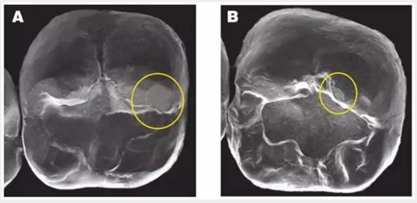

2. 牙冠對(duì)對(duì)頜牙造成的磨損:這三種冠材料與對(duì)頜牙的接觸中都會(huì)造成小的磨損平面(加下圖)BruxZir 的磨損平面更大也更多。這些修復(fù)體使用一年后出現(xiàn)的磨損平面,需要更多的時(shí)間去觀察。(見(jiàn)下圖)

圖像A和圖像B 顯示了Bruxzir和切削類(lèi)e.maxCAD全冠對(duì)對(duì)頜牙造成的磨損平面。本次研究中所有的材料(包括控制對(duì)照組)都會(huì)一些造成類(lèi)似的小磨損平面。無(wú)論對(duì)頜牙是釉質(zhì)、鑄造金屬、復(fù)合樹(shù)脂還是瓷。

圖像A顯示了對(duì)頜牙在BruxZir全鋯冠上造成的磨損的平面,黃色圓圈代表復(fù)合樹(shù)脂和釉質(zhì),橙色圓圈代表瓷。圖像B顯示了對(duì)頜牙為鑄造金屬修復(fù)體時(shí),對(duì)切削類(lèi)e.maxCAD單冠造成的磨損平面。兩種牙冠表面都有小的磨損平面,而且他們的對(duì)頜牙都顯示出了良好的結(jié)果。臨床上,對(duì)頜牙的每種材料(瓷、樹(shù)脂、釉質(zhì)、鑄造金屬)被磨損的程度幾乎是等同的。